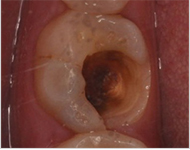

材料填充,即时雕刻外形,除去超过咬合面过高的部分,以防刺激牙龈引起炎症。